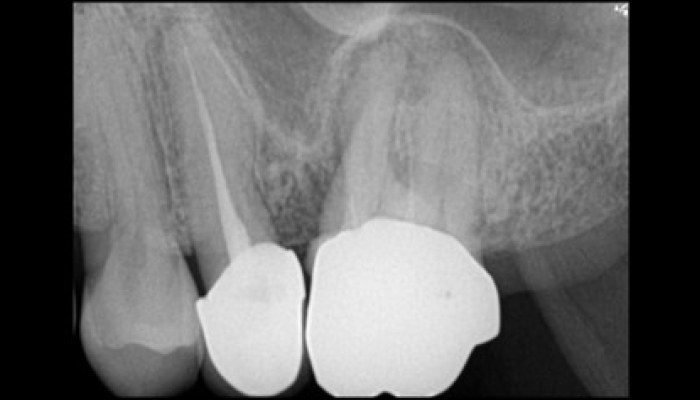

다양한 합병증을 동반하는 이갈이

서울바른훈치과에서는 임상검사 및 바이트스트립, 필요시 치과에서 제작한 이갈이 검사장치를 이용하여 이갈이를 정확하게 진단하고 이와 동반된 치아시림, 턱관절장애, 안면부 근육통, 두통, 사각턱까지 총체적으로 치료가 가능합니다.